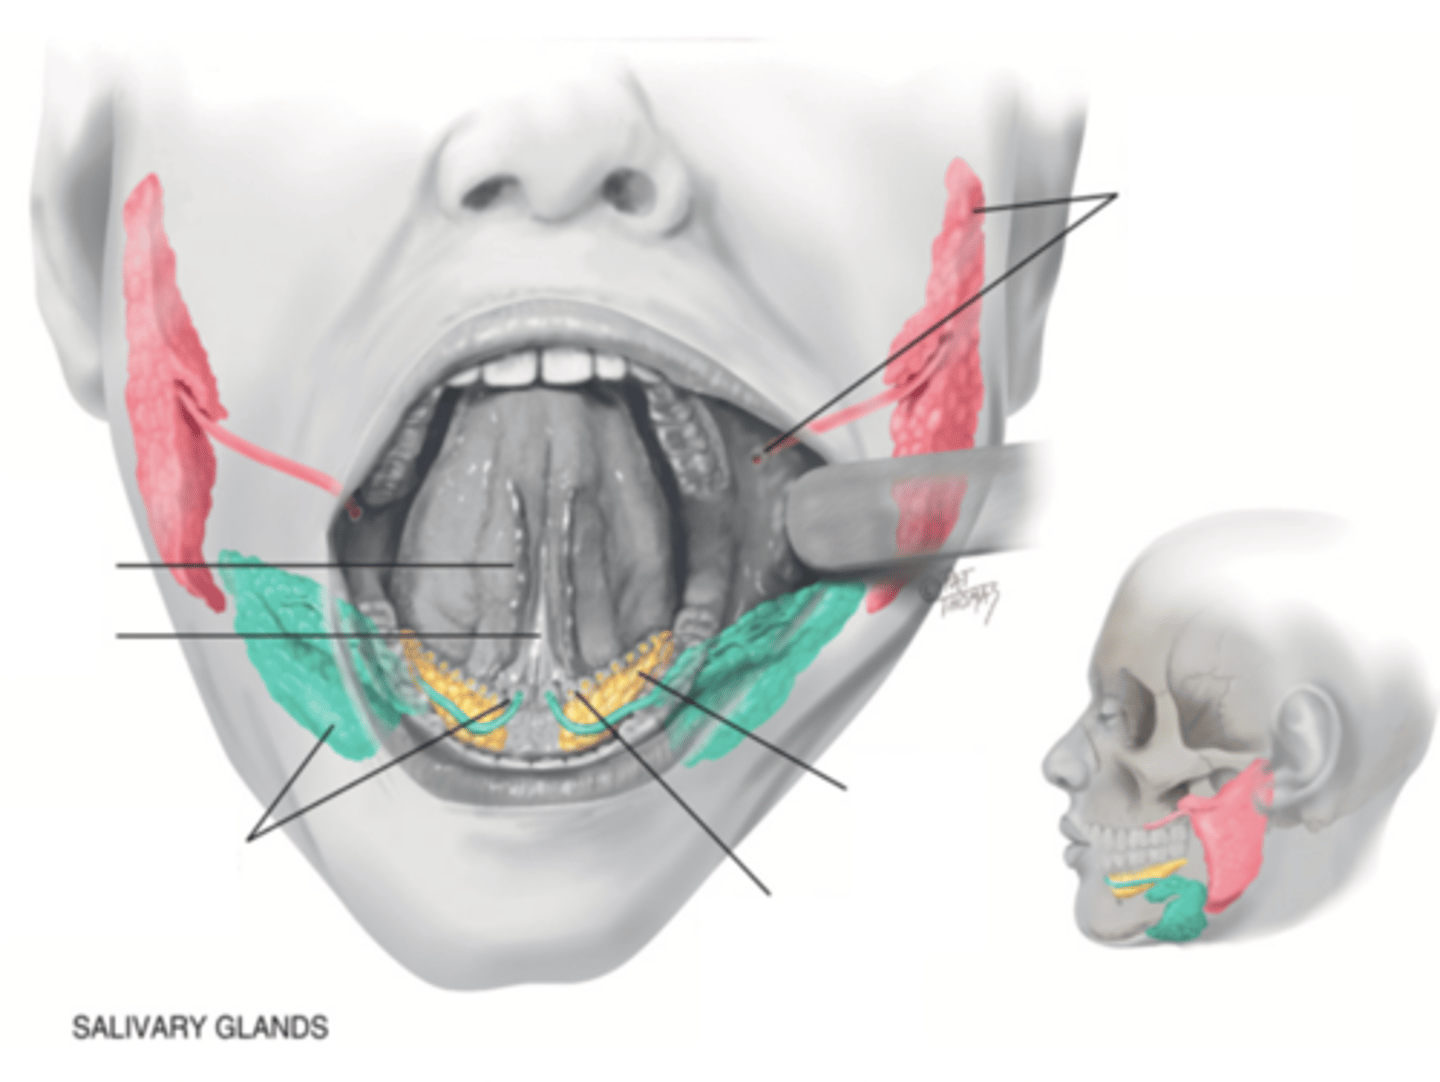

Salivary Glands

- Parotid

- Submandibular

- Sublingual

Parotid Gland

Salivary gland within the cheek, just anterior to the ear (red)

Submadibular Gland

Salivary gland under the mandible (green)

Sublingual Gland

Salivary gland under the tongue (yellow)